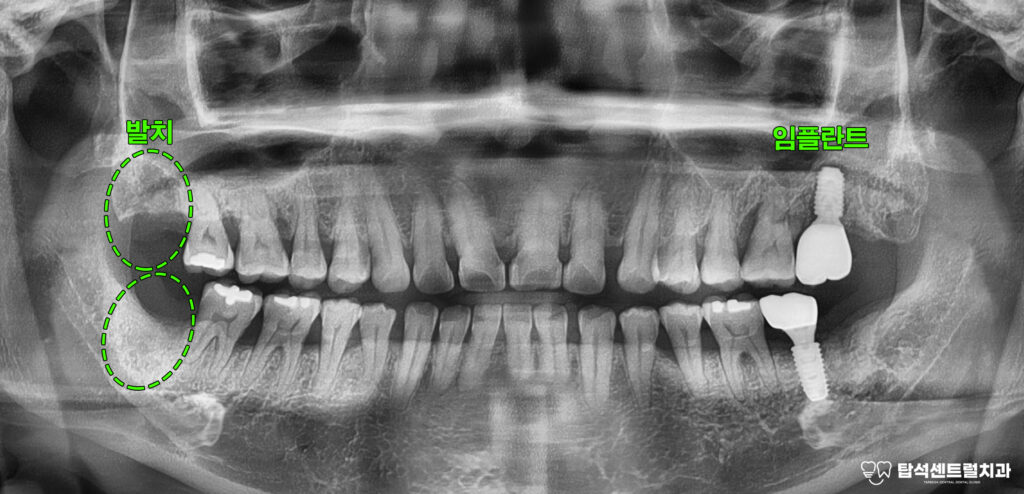

고산동 치과 케이스에서

말씀드린 해당 부위들을

발치한 후에는 치조골 소실량을

정밀하게 평가해야 됩니다.

윗니의 경우 발치와 보존술을 시행한 뒤

약 4개월 간 치유 기간을 거쳐

지연 식립 방식으로 진행하는 것이

안전합니다.

해당 방법은 이를 뽑은 자리에

골이식재를 채워 넣어 뼈가 흡수되는

것을 최소화하는 술식을 의미합니다.

반면 아래턱 치아는 발치 즉시 식립이

가능한데, 이는 치조골 상태가 비교적

양호하고 초기 고정력을 확보할 수 있기 때문입니다.

흔들리는 18번과 48번 사랑니 역시

발거가 필요한 상태였습니다.

그동안 사랑니도 함께 뽑아낸

모습이 확인되고 있습니다.